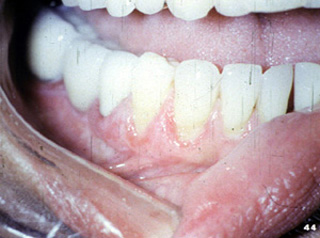

| El

examen de otras áreas de la cavidad oral reveló áreas en placa de

color blanco. Las biopsias del tejido adyacente a las áreas ulceradas

así como las lesiones blancas fueron hechas en ese orden para

hacer un diagnóstico definitivo y descartar la posibilidad de pénfigo

vulgar o penfigoide. Estas biopsias fueron interpretadas como liquen plano erosivo.